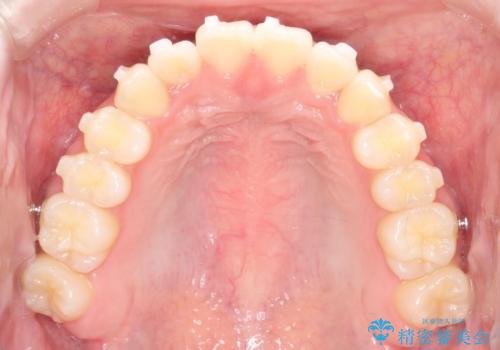

【インビザライン】前歯のガタガタをなおしたい

- 前歯のガタガタを主訴に来院されました。

開咬ぎみであったため、しっかりと前歯が噛むように計画を立てて治療をおこないました。

仕上がりも良く、患者様にも満足していただきました。

インビザラインは前歯を噛ませるような開咬の治療も得意としています。